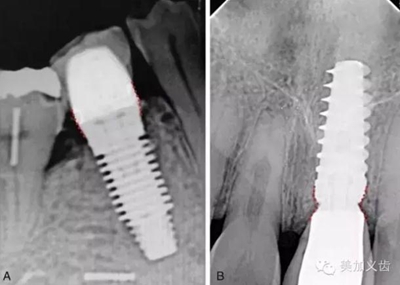

2.jpg

根尖片屬于最最基本的口腔二維影像學(xué)檢查,很難看到重要的解剖部位,除非采用嚴(yán)格的平行投照技術(shù),否則拍攝角度的變化對測量數(shù)值的準(zhǔn)確性有很大的影響。

其優(yōu)點是:分辨率高,能看到局部細節(jié),費用比較低,患者都能夠接受,而且操作也比較簡單,醫(yī)生和護士都能很快學(xué)會,放射劑量相對很小,對醫(yī)生和患者的影響都不大,國外已經(jīng)普遍在診室拍攝根尖片了,國內(nèi)還沒有得到允許。

其缺點是:看到的范圍實在是太小了,無法用來評估術(shù)區(qū)骨量的多少,而且因為拍攝角度的問題,尤其是上后牙,你肯定見過某些上6的顎根已經(jīng)長到上頜竇里了,其實并沒有,只是拍攝角度所導(dǎo)致。如果僅僅通過根尖片檢查就開展種植,其風(fēng)險可想而知,可以說是對患者和自己都不負責(zé)任的做法。

但根尖片是種植中必不可少的檢查,可以用來檢查基臺與種植體、修復(fù)體與基臺之間的密合程度,或者用于術(shù)后隨訪。

值得注意的是:使用根尖片來進行術(shù)后隨訪,這是種植術(shù)后很重要的一件事情,而且需要定期來做,然后將拍攝出來的根尖片進行對比,才能看到是否有骨吸收。但如果你每次拍攝的角度都不一樣,結(jié)果會讓你嚇一跳,怎么某段時間內(nèi)骨吸收這么多?!怎么某段時間骨頭又長上來了?!太令人費解了!